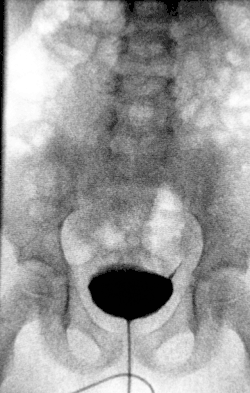

Untersuchungen, die zur Abklärung einer Hydronephrose eingesetzt werden, sind Sonografie, intravenöse Pyelographie, Miktionszystourethrographie und Szintigraphie (zur Beurteilung der Nierenrestfunktion).